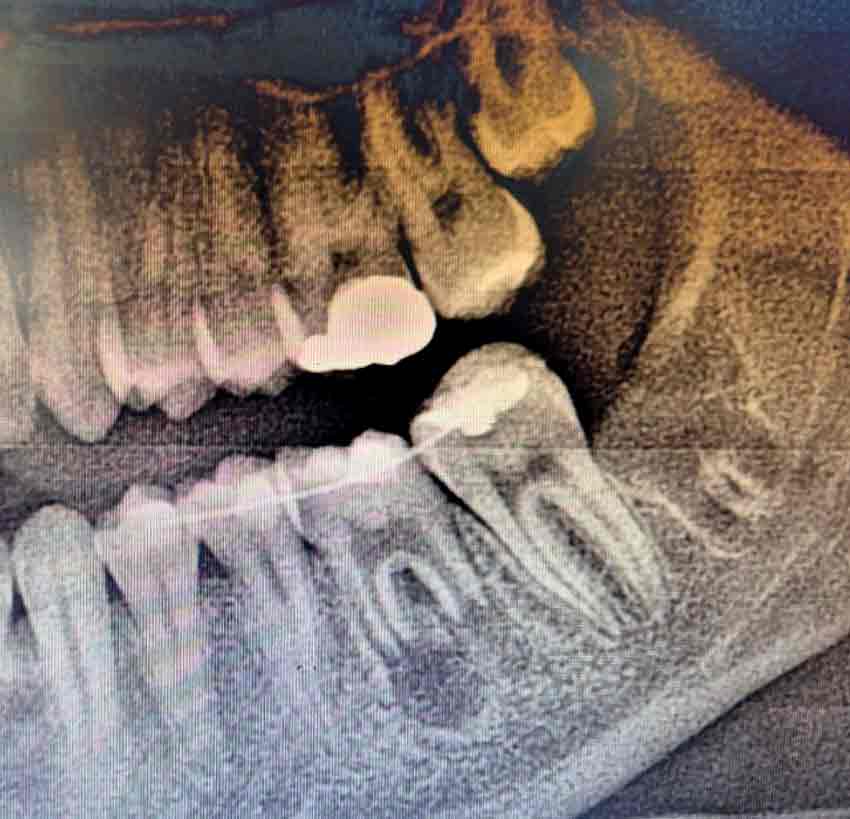

Hastaneden yapılan açıklamada operasyonun detayları şu şekilde paylaşıldı. Genç bir hastanın tüm tedavi uygulamalarına rağmen kurtarılamayan daimi azı dişi, tedavi amacıyla çekildi. Ancak çocuk yaşta çene gelişimi devam ettiği için implant uygulaması gibi klasik tedavi yöntemleri uygun görülmedi. Bu nedenle hastanın kendi ağzında, kemik içinde gömülü halde bulunan üçüncü azı dişi (yirmi yaş dişi), operasyon mikroskobu eşliğinde cerrahi olarak çıkarıldı ve hazırlanan çekim yuvasına nakledildi. Ayrıca dişin daha sağlıklı bir şekilde iyileşebilmesi için hastanın kendi kanından elde edilen PRF (Platelet Rich Fibrin) biyomateryali, nakil işlemi öncesinde hazırlanan yuvaya yerleştirildi.”